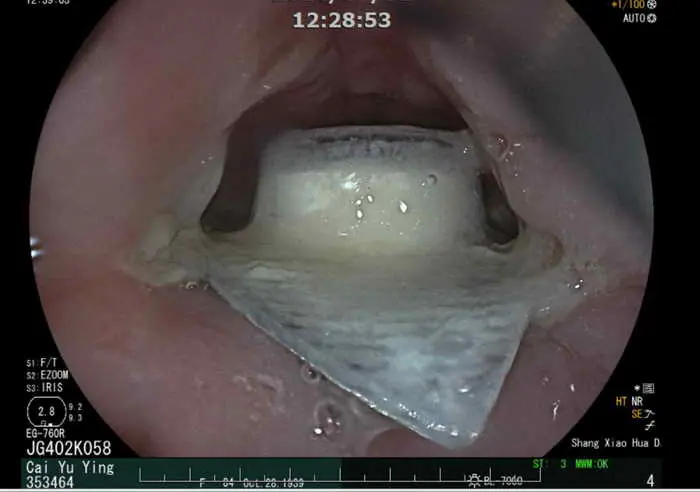

【記者張德欽、張珊瑜、張文煌、林慶文/南投報導】有部分民眾為了分裝方便,會使用剪刀將排裝的藥丸剪成一個一個小方塊的形狀,但這樣其實會增加誤食的風險。南投一名84歲蔡阿嬤日前在吞藥時,就不小心把藥丸連同其鋁箔包裝一起吞下肚,結果食道被尖銳鋁箔片哽住,造成食道潰瘍。所幸透過內視鏡順利取出異物,治療後恢復情況良好。醫師提醒誤食尖銳物可能會造成食道發炎穿孔甚至是腸穿孔的危險,建議若不慎吞入異物,喝水後仍異物感明顯未達緩解,則建議就醫接受檢查治療。

84歲蔡阿嬤在家人陪同下,至衛生福利部南投醫院洪弘昌院長的肝膽腸胃科門診就診,阿嬤向院長表示自己的喉嚨痛了一個禮拜,且總是卡卡的,有明顯異物感。洪弘昌院長細心問診下,得知阿嬤有使用剪刀切割藥物的習慣,因為藥品的包裝材質較硬,被切割後邊緣較鋒利,懷疑老人家不慎連同包裝誤食而卡住。透過內視鏡檢查發現藥丸的鋁箔片包裝就卡在食道上,安排住院以胃鏡取出異物並且藥物治療,治療食道潰瘍及預防感染。

肝膽腸胃科黃耀光醫師表示,民眾常見誤食的異物有魚刺、雞骨頭或假牙,大部分的異物會自然排出,但少部分尺寸較大或較尖銳的異物可能會導致食道黏膜受傷甚至穿孔。穿孔可能引發縱膈腔炎或造成食道-氣管廔管或刺穿主動脈形成主動脈-食道廔管,未即時處置可能會有生命危險。黃耀光醫師表示,所幸這名患者誤吞的異物僅造成食道黏膜受傷,尚未造成穿孔等嚴重併發症。

圖文:阿嬤吃藥不慎連鋁箔包裝一起吞下 卡食道就醫透過胃鏡取出。